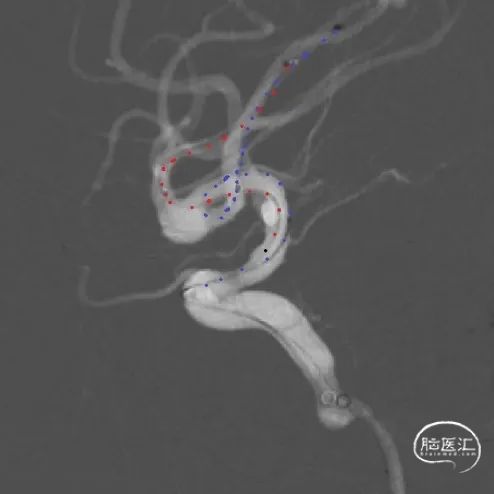

将3mm*21mm Atlas支架通过上干微导管输送到位,对位准确后,通过微导管成功释放。

释放完第一枚支架的SL-10微导管(蓝管)留在M1水平段不撤出,然后用微导丝将其引导穿过第一枚Atlas支架的网眼超选入MCA下干的另一分支,微导丝及微导管穿网眼过程中Atlas支架稳定。成功穿网眼建立第二枚支架通路后,将备用的SL-10微导管(红管)轻轻后撤,管头正好从下干落入动脉瘤腔内,留待填塞弹簧圈用。

经下干的SL-10微导管释放第二枚Atlas支架,形成“Y”型支架形态,充分保护上下两干,Atlas支架打开顺畅,影像下可清晰看到两端标记点完全打开。第二枚支架释放完毕后,顺势将该SL-10微导管经支架网眼顺利超选入瘤腔,拟双微管填塞。经一根SL-10微导管释放第一枚Target XL 4mm*12cm弹簧圈进行成篮。